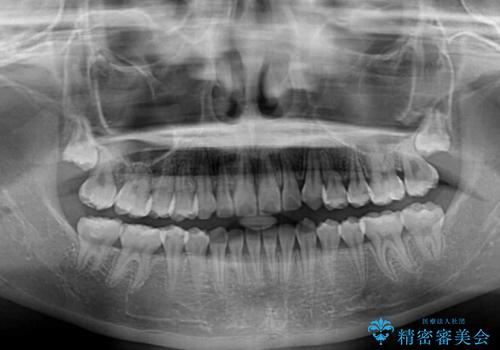

外側を向いていた奥歯は比較的早い時期に歯列に収まり、咬み合わせも磨きやすさも改善することができました。

歯列は元々悪くなかったので、1年ほどで治療を終えることができました。